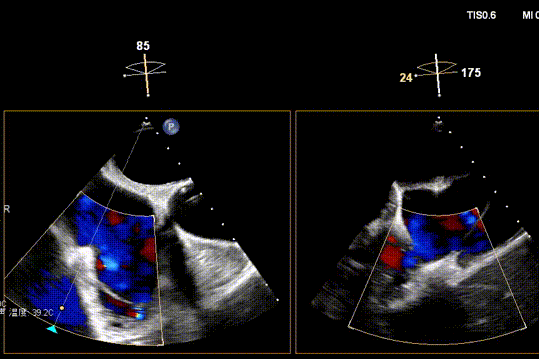

Surgical Outcome

1. Regurgitation Effect: Reduced from massive (5+) to moderate (2+).

Preoperative

Postoperative

2. Annuloplasty Effect:

Ultimately, the tricuspid annulus was significantly reduced, and regurgitation was downgraded from critical to mild‑to‑moderate.